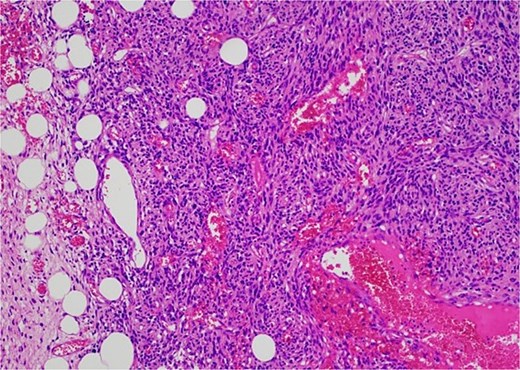

Histology revealed a multilobulated spindle cell lesion, with low- and high-grade areas, with an abrupt transition between these areas. There was an adjacent focus of adipose tissue with rare cytologic atypia suggestive of possible WDL, which indicated that the tumor mass may represent DDL. However, there was a single focus of lipoblasts identified, bringing up the differential of pleomorphic liposarcoma. Therefore, in situ hybridisation was performed and showed MDM2 amplification, which confirmed the diagnosis of DDL, with likely homologous lipoblastic morphology. The tumour was excised with clear margins (Figs 3–8).

The high-grade component demonstrates increased cellularity, hyperchromasia and moderate to marked pleomorphism including scattered multinucleate cells.